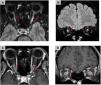

The aim of this work is to provide a diagnostic approach to the potential causes of optic neuropathy, focusing on the radiological findings associated with this pathology. Various etiologies have been identified, including inflammatory and demyelinating optic neuritis, developmental and hereditary diseases, neurodegenerative disorders, infectious conditions, post-traumatic causes, ischemic optic neuropathy (with anterior ischemic optic neuropathy being the most common form), and neoplastic etiologies. Optical coherence tomography and magnetic resonance imaging play a fundamental role in the diagnosis of optic neuropathy, allowing to distinguish patterns of optic nerve involvement. These studies are essential to locate and characterize the different pathologies, increasing the precision of the diagnosis in diseases presenting optic neuropathy as the main symptom. In conclusion, the findings obtained from magnetic resonance imaging are essential in the differential diagnosis of optic nerve diseases, aiding in the localization and characterization of various pathologies affecting either the optic pathway alone or multiple levels of the central nervous system and thereby increasing diagnostic accuracy.